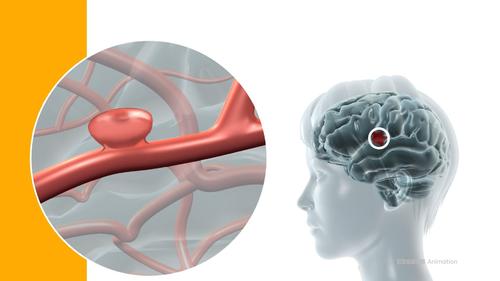

Lebensgefährlich und oft unentdeckt

So entsteht ein Aneurysma im Kopf